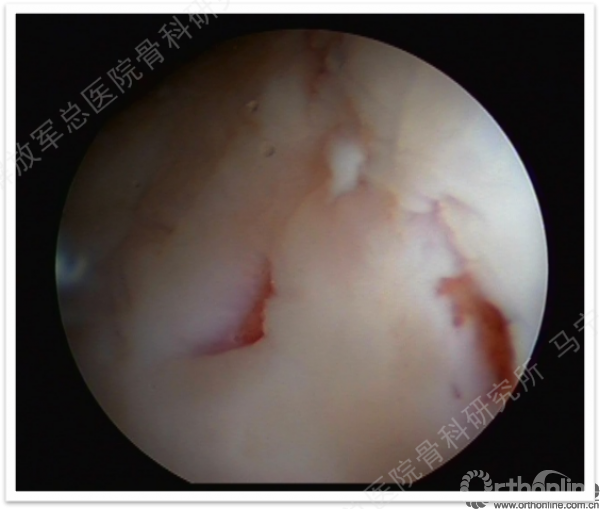

第一次手术-评估(关节镜评估及取种子细胞)。

缺损部位的标记:根据关节镜下的检查评估来确定损伤部位,范围,以决定二次手术的切口部位。

软骨组织的获取:关节镜下观察关节软骨的股骨髁间非负重区的穹窿部位或股骨滑车区边缘非负重部位,清理周围的滑膜组织,应用髓核钳或鹅眉凿获取患者关节软骨100-200mg。